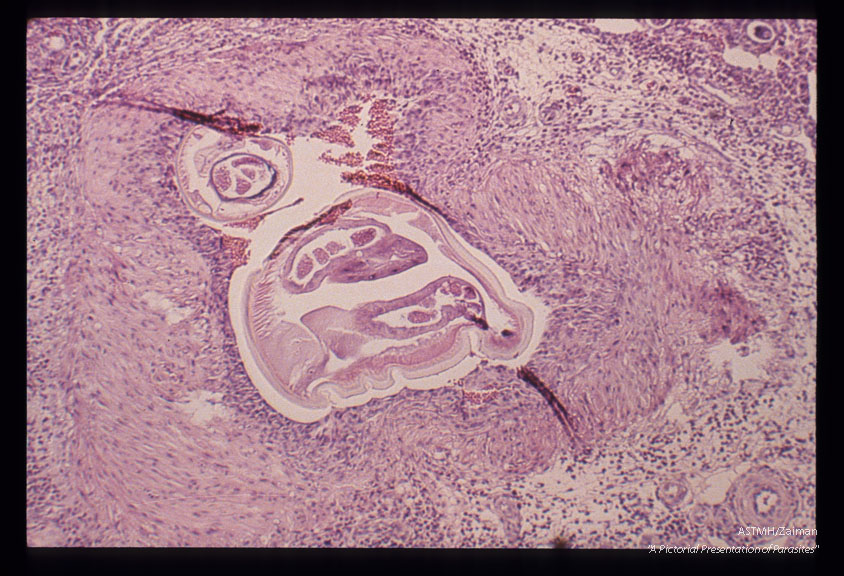

Microscopic views of rat lung reaction to the nematodes.

Angiostrongylus cantonensis

Description: Microscopic views of rat lung reaction to the nematodes.